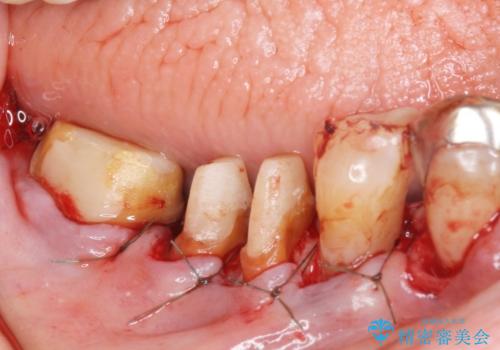

- 歯ぐきからの出血と腫れを主訴に来院された患者様です。

プラークコントロールが非常に悪く、全顎的な歯周病に罹患していました。

「抜歯したくない、インプラントは嫌」という患者様のご希望とご年齢を考慮し、可及的な骨外科処置や根分割術によりできるだけ今ある歯を残す治療方針をたてました。

長期的な予後は保証できないことをご了承頂いた上で治療を行いました。